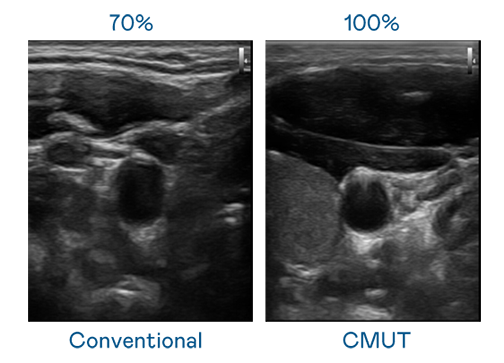

CMUT 技术是一种用电容式微机电元件来产生超音波讯号的技术。与传统 PZT 压电式技术相比,CMUT 频宽增加 30%,更宽频的超音波讯号让影像解析度大幅提升,是实现高影像品质医疗超音波扫描、促进精准医疗发展的关键技术。

超音波影像的解析度高低,首先取决于探头能发出的讯号频宽。成人看片7777.tv CMUT 可提供高清晰的超音波讯号,提供高频宽、高灵敏度、影像纹理细节更高的超音波影像,协助医护人员缩短影像判读时间及利用精准的医疗影像进行诊断。